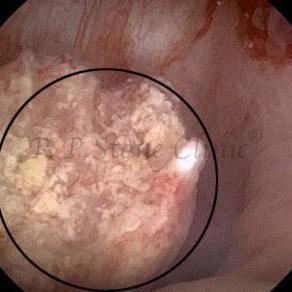

Kidney stone is a solid mass of CRYSTALS. It is the process of crystallization which initiates the formation of kidney stones. This happens in nephrons or units of kidney. Once a small crystal is formed, it can both grow & unite with other crystals leading to the formation of small concretion which eventually forms a stone. Once these large crystals detach from the collecting ducts, the process of stone formation starts in the renal collecting system. A recurrent kidney stone former is advised to know a little bit about something known as Randall’s plaque. Alexander Randall discovered plaques on the renal papillae eight decades back based on examination of 1154 pairs of autopsied Kidneys. He described these renal papillary lesions as cream colored or milk patch areas composed of calcium phosphate & calcium carbonate. These plaques could act as NIDUS for formation of KIDNEY STONE. Calcium Oxalate stone can form on this nidus & then detaches from this plaque to become a free floating stone in the collecting system of kidney

These images are taken as snap shots from the video recording of RIRS Surgery done at our hospital. These are Randall’s Plaques seen with Digital FLEX XC & Digital FLEX XC S. The cream or whitish patches are seen on the tips of RENAL PAPILLAE as seen in images below.

Randall’s Plaques may lead to the formation of Stones.

Those kidney stone patients who have Randall’s Plaques in their kidneys are more likely to form stones again (Recurrent Stones).

Stone Patients in whom Randall’s Plaques are detected at the time of RIRS Surgery should undergo regular ultrasound examination for early detection of stones.